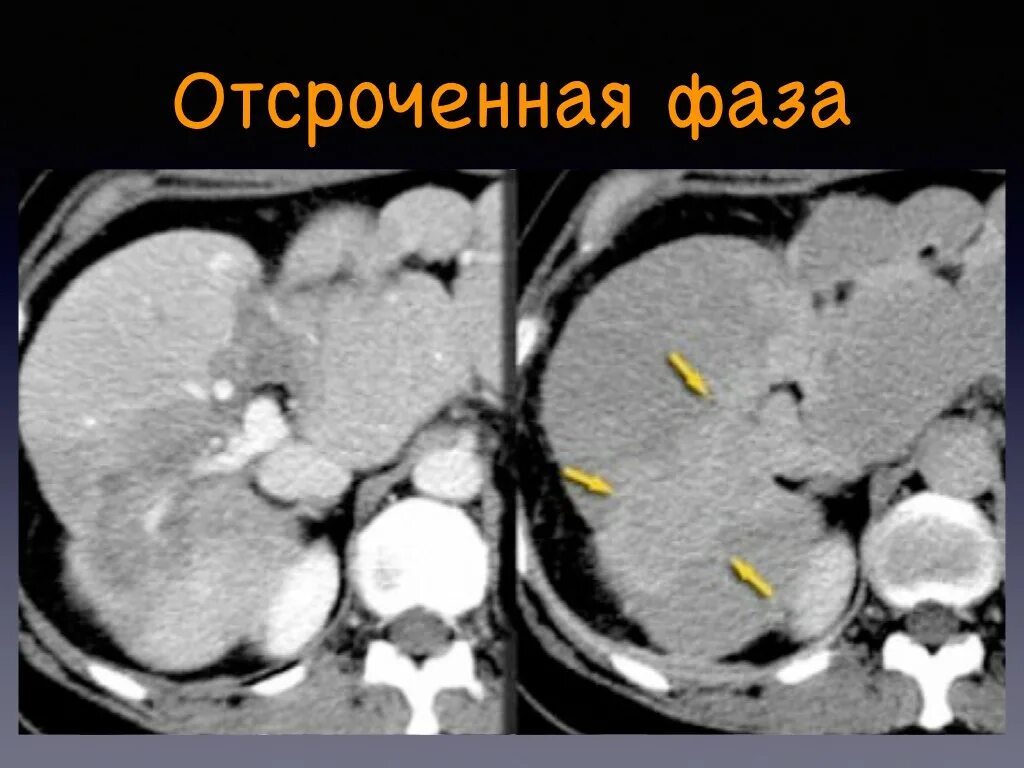

Плохо после контраста кт